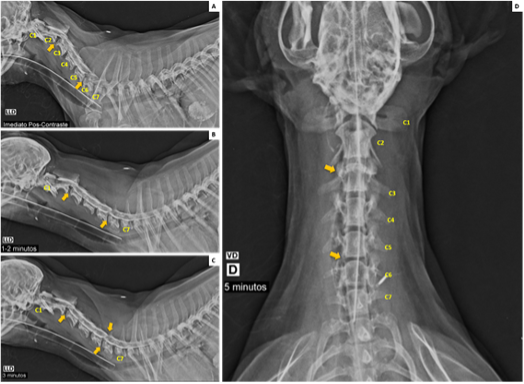

Takayasu's Arteritis and Double Right Renal Artery: A Previously Unreported Association

Mauer Alexandre da Ascensão Gonçalves, Humberto Morais, Miguel Bernardino Antunes Vicente, Capela Pascoal, Tshimbalanga Merite

bjcr86